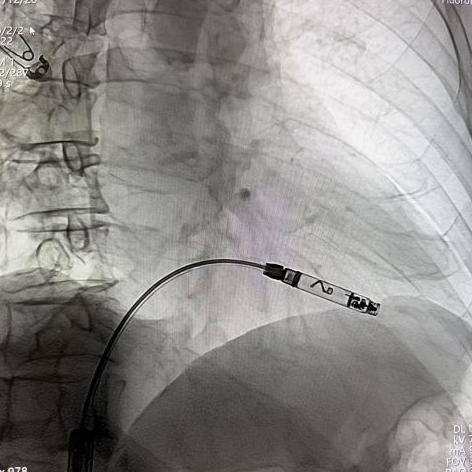

通过股静脉穿刺,建立血管通路,经导丝送入猪尾导管至右心房,分别在RAO 30°和LAO 30°进行右心耳造影,确认目标位置。

右心耳LAO造影